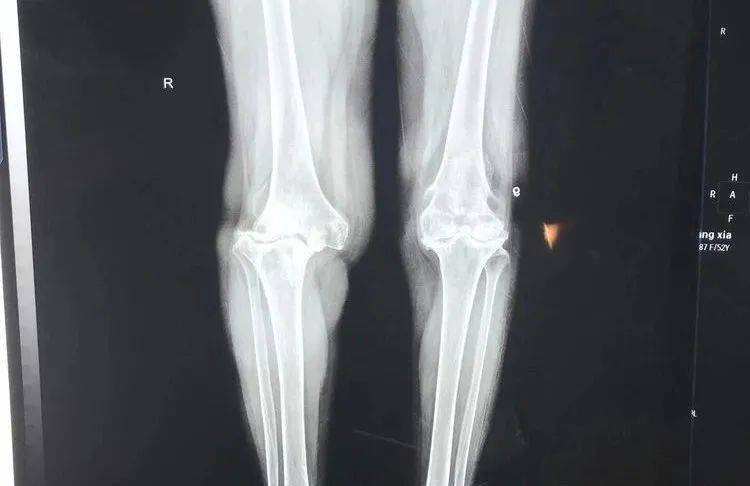

膝关节置换医院排名_膝关节置换图片

基层医院进行的一例膝关节置换,请大家指点